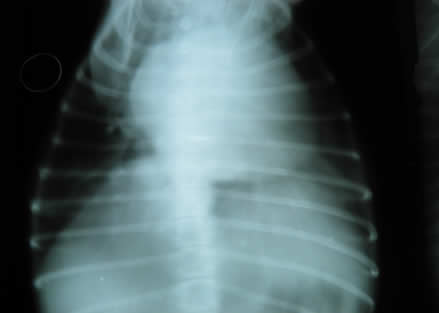

• Radiografías de tórax para observar los pulmones, la forma y tamaño del corazón.

En nuestra clínica contamos con equipos diagnósticos adecuados para abordar y diagnosticar estas enfermedades, por ejemplo electrocardiograma, rayos x, ultrasonido y una preparación constante en esta área. Además tenemos un servicio anexo de cardiología para abordar enfermedades complejas y que necesitan equipos de diagnostico y conocimientos mas especializados.

Rayos en mascotas Rayos en mascotas